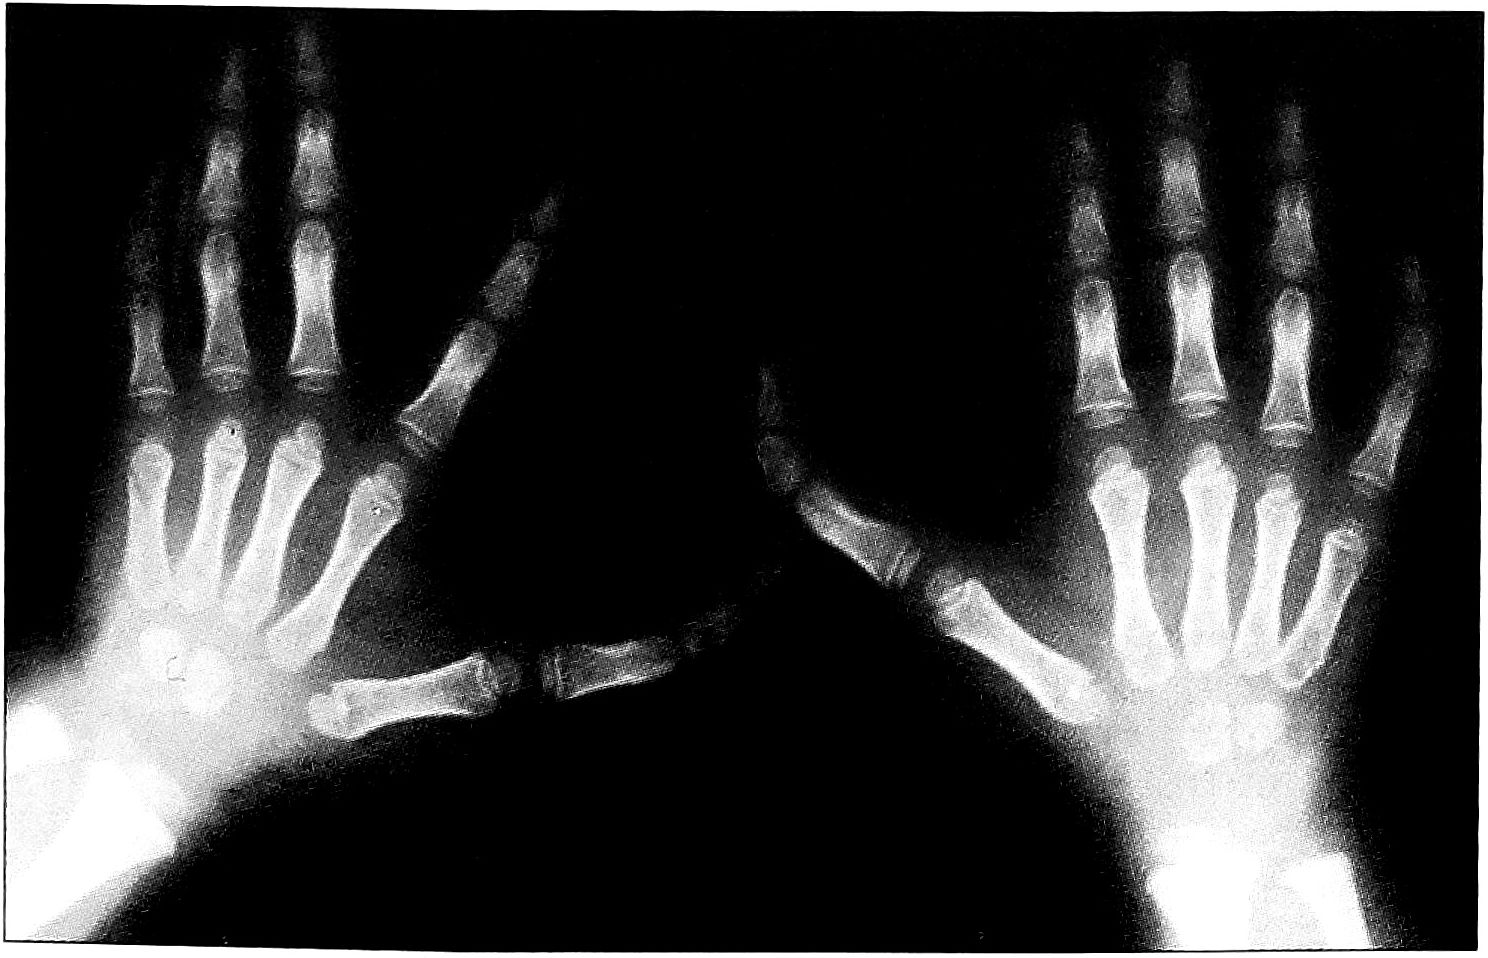

- Сочетание трехфалангизма с радиальной полидактилией. Нами выделено два варианта сочетания трехфалангизма с радиальной полидактилией: 1) с изолированным поражением кисти; 2) с поражением предплечья и кисти.

В 1-й группе выявлены следующие разновидности (рис. 7): трехфалангизм в сочетании с радиальной полифалангией; трехфалангизм в сочетании с неполным (полным) удвоением (утроением) I луча; трехфалангизм в сочетании с радиальной и центральной полидактилией (вариант «зеркальной кисти»). 2-я группа была представлена трехфалангизмом I пальца кисти в сочетании с радиальной и центральной полидактилией, а также аномалией развития костей предплечья (вариант «зеркальной кисти») (рис. 8).

Рис. 7. Сочетание трехфалангизма с радиальной полидактилией и изолированным поражением кисти. а — трехфалангизм в сочетании с радиальной полидактилией; б — трехфалангизм в сочетании с полным удвоением I луча; в — трехфалангизм в сочетании с неполным утроением I луча; г — трехфалангизм в сочетании с радиальной и центральной полидактилией кисти без аномалии развития предплечья.

Рис. 8. Трехфалангизм I пальца кисти в сочетании с радиальной и центральной полидактилией, а также аномалией развития костей предплечья.

Брахимезофалангеальные и долихофалангеальные формы трехфалангизма основного и дополнительного лучей с характерными признаками, описанными выше, в 1-й группе больных встречались с примерно одинаковой частотой, нередко отмечалась гипоплазия дополнительных I лучей. Во 2-й группе наблюдались лишь долихофалангеальные формы.